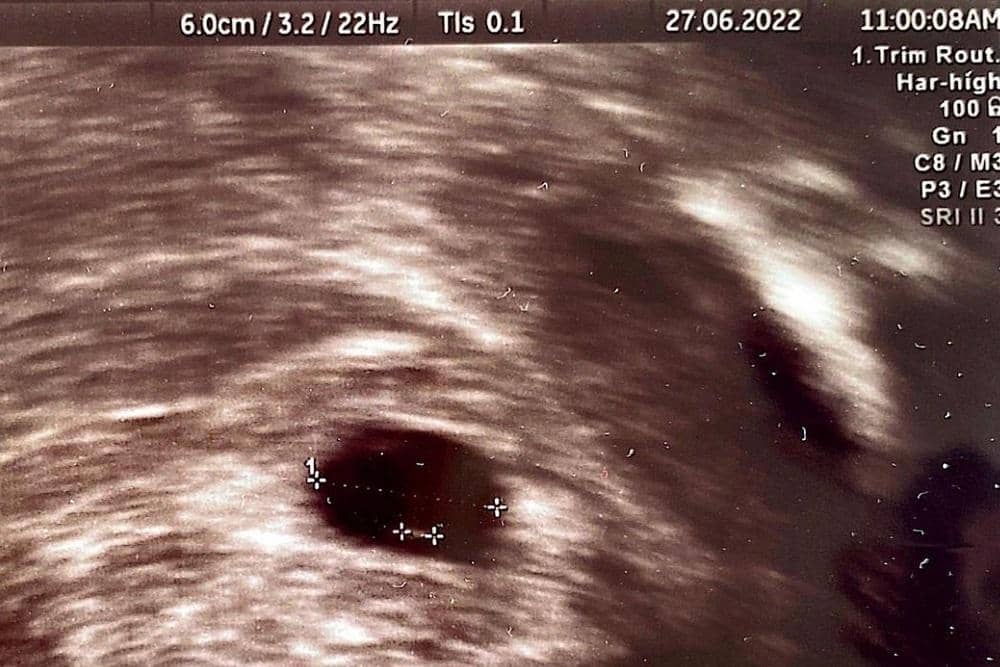

Berita bahagia itu tidak berlangsung lama. Dokter menyatakan kehamilan Annisa Pohan bermasalah. Janin yang sedang dikandungnya tidak berkembang di usia 7 minggu.

“Namun qadarullah, mungkin Allah punya rencana lain yang lebih baik. Kehamilan saya dinyatakan tidak berkembang di usia 7 minggu, ukuran baby-nya terlalu kecil dan tidak ada detak jantungnya, sehingga tidak dapat dipertahankan,” tulis Annisa.